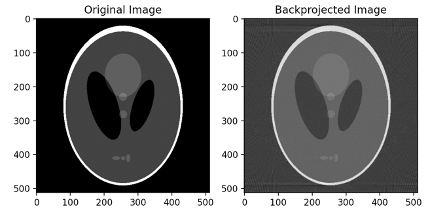

2. Filtered backprojection algorithm

Lterative algorithm의 단점으로 인해 대부분의 CT가 이 방식을 따릅니다. 각도별로 projection해 sinogram을 만들고 filter를 곱해 filtered된 sinogram을 만듭니다. 그 다음 back-projection을 수행합니다.